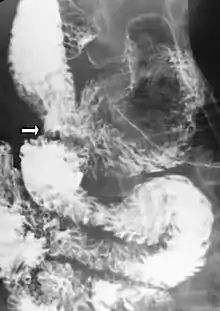

Upper gastrointestinal series showing extreme duodenal dilation (white arrow) abruptly preceding constriction by the SMA.

Upper gastrointestinal series showing extreme duodenal dilation (white arrow) abruptly preceding constriction by the SMA.- Ultrasound showing SMA syndrome[18]